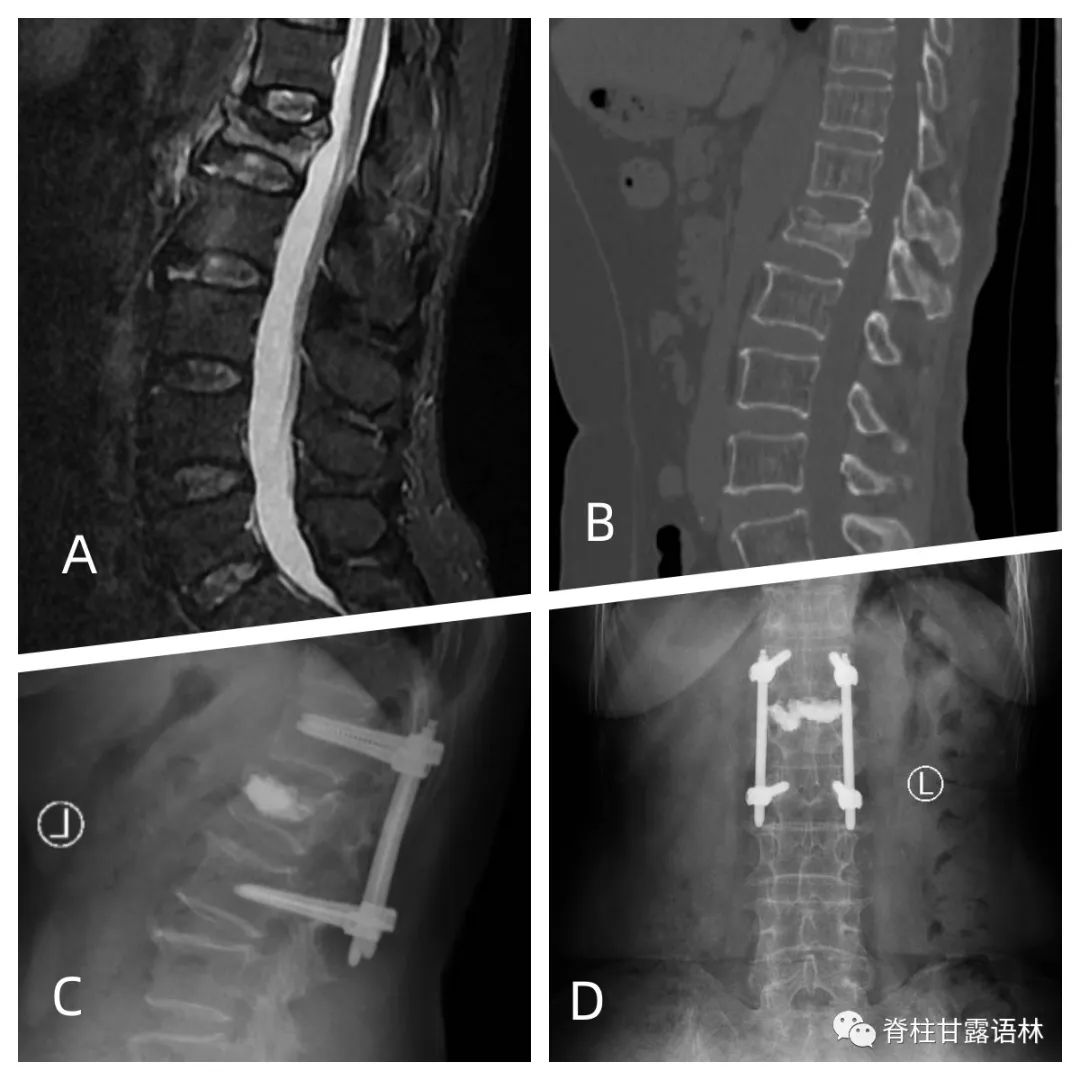

女,65岁,外伤致L1椎体爆裂骨折。A, 术前MRI显示L1椎体骨折,后方韧带复合体损伤,TLICS评分4分。B, 术前CT示L1骨折,椎体后上角轻度向后移位。C、D, 后路短节段经皮椎弓根螺钉固定+PVP术后3月复查正、侧位X线。当椎体爆裂骨折需要前柱支持时,后路固定联合椎体骨水泥增强已被使用。后路短节段椎弓根螺钉固定和PKP术可改善椎体高度的恢复,减少后凸畸形,并在最终随访时保持矫正效果。[18,25]